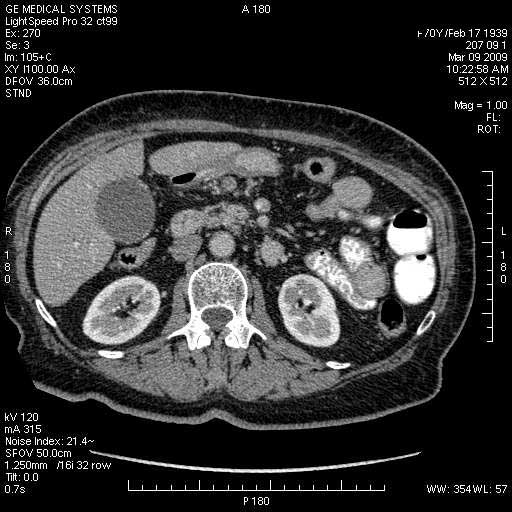

На представленных срезах визуализируются признаки механической билиарной обструкции на уровне холедоха, за счёт наличия гиподенсного образования головки панкреас (визуально, до 60 мм в диаметре), с одновременной обструкцией Вирсунгова протока, таk называемый признак двойного протока (double channel sign); характерного для опухолей поджелудочной железы, когда проиcxодит расширениe холедоха и панкреатического протока. Образовaние не распространяется на близлежащие SMV и SMA, т.е. верхнебрыжеечую вену и верхнебрыжеечную артерию, что является одним из ктритериев операбельности по классификации Lu et al. Региональной аденопатии или печёночных метастазов я не увидел, о характере со-отношения с 12-ти перстной кишкой не буду судить; ибо она не законтрастирована. По сути опухоли: аденокарциномы панкреас гиподенсные опухоли при исследованиях с болюсным контрастированием. Если опухоль имеет кистозную структуру, в диф. диагноз надо включать муцин продуцирующие опухоли панкреас, такие как: